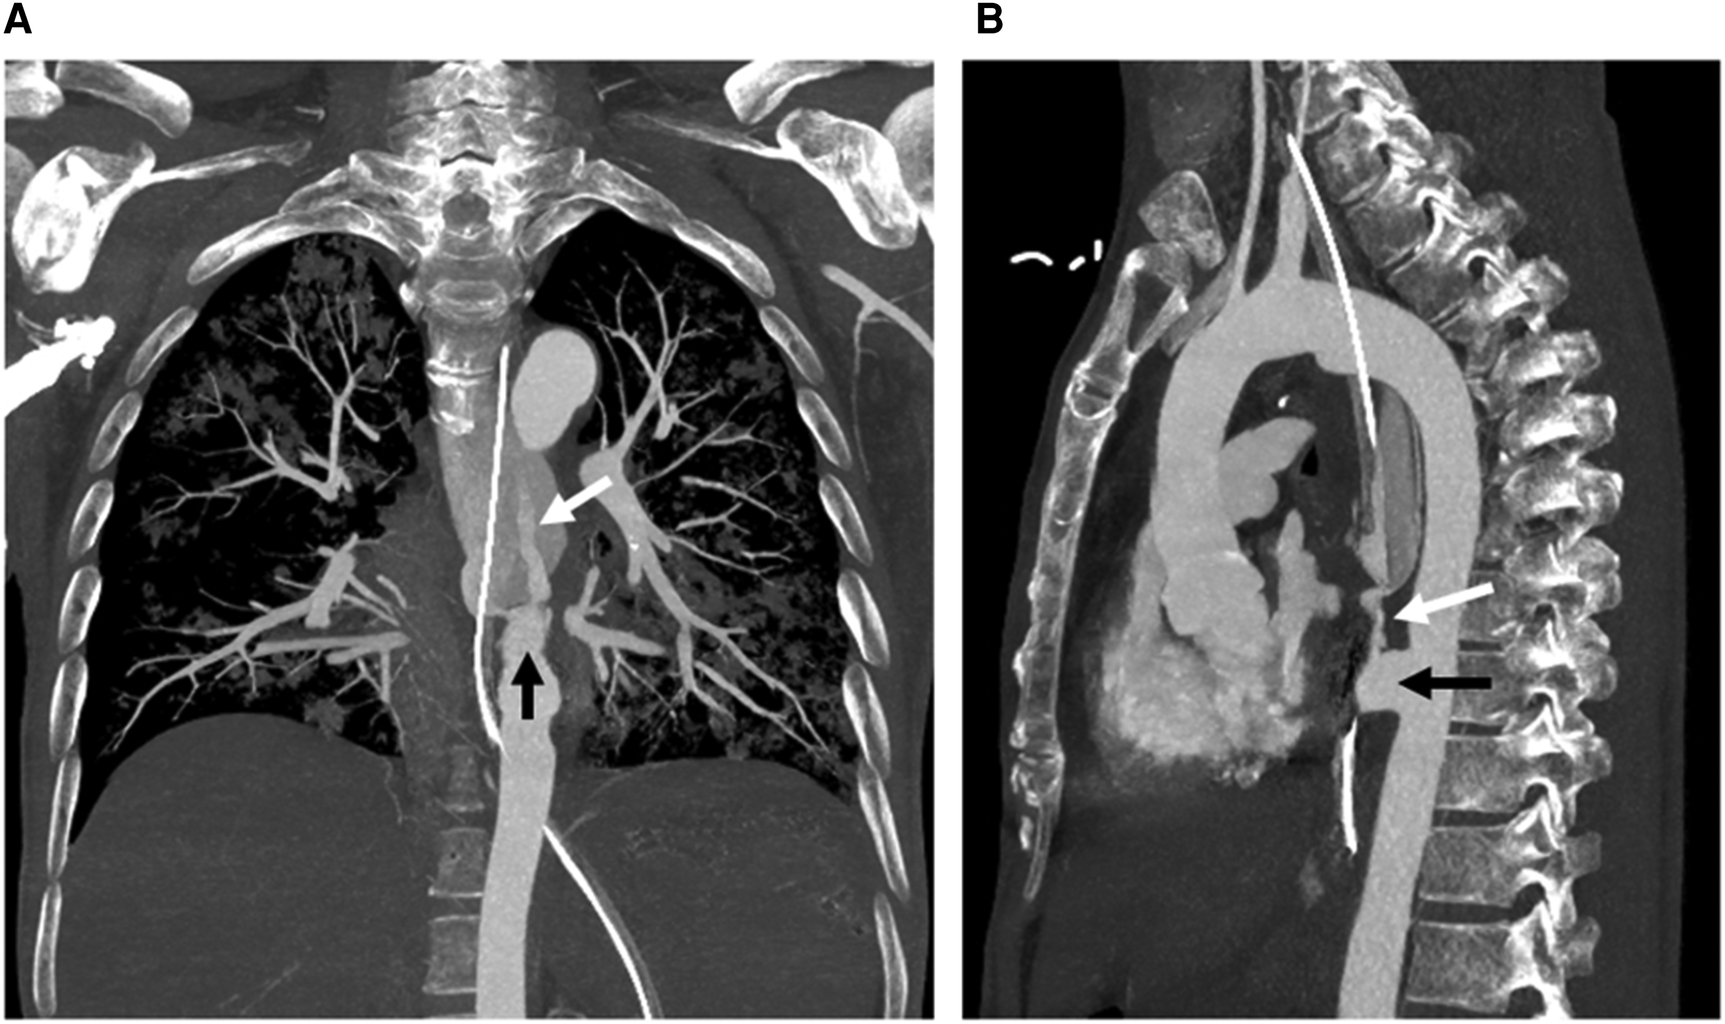

Figure 2. Coronal (A) and sagittal (B) maximum intensity projection images from computed tomography angiography show a descending aortic pseudoaneurysm (black arrow) at the level of the aortoesophageal fistula, complicated with rupture and contrast material extravasation (white arrow) into the esophagus (with a nasogastric tube in situ).